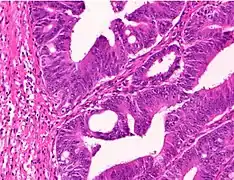

Adenocarcinoma is a malignant epithelial tumor, originating from superficial glandular epithelial cells lining the colon and rectum. It invades the wall, infiltrating the muscularis mucosae layer, the submucosa, and then the muscularis propria. Tumor cells describe irregular tubular structures, harboring pluristratification, multiple lumens, reduced stroma ("back to back" aspect). Sometimes, tumor cells are discohesive and secrete mucus, which invades the interstitium producing large pools of mucus. This occurs in mucinous adenocarcinoma, in which cells are poorly differentiated. If the mucus remains inside the tumor cell, it pushes the nucleus at the periphery, this occurs in "signet-ring cell." Depending on glandular architecture, cellular pleomorphism, and mucosecretion of the predominant pattern, adenocarcinoma may present three degrees of differentiation: well, moderately, and poorly differentiated.[5]

- Invasive adenocarcinoma commonly displays:[6]

- Varying degrees of gland formation with tall columnar cells

- Dirty necrosis, consisting of extensive central necrosis with granular eosinophilic karyorrhectic cell detritus.[6][7] It is located within the glandular lumina,[7] or often with a garland of cribriform glands in their vicinity.[6]